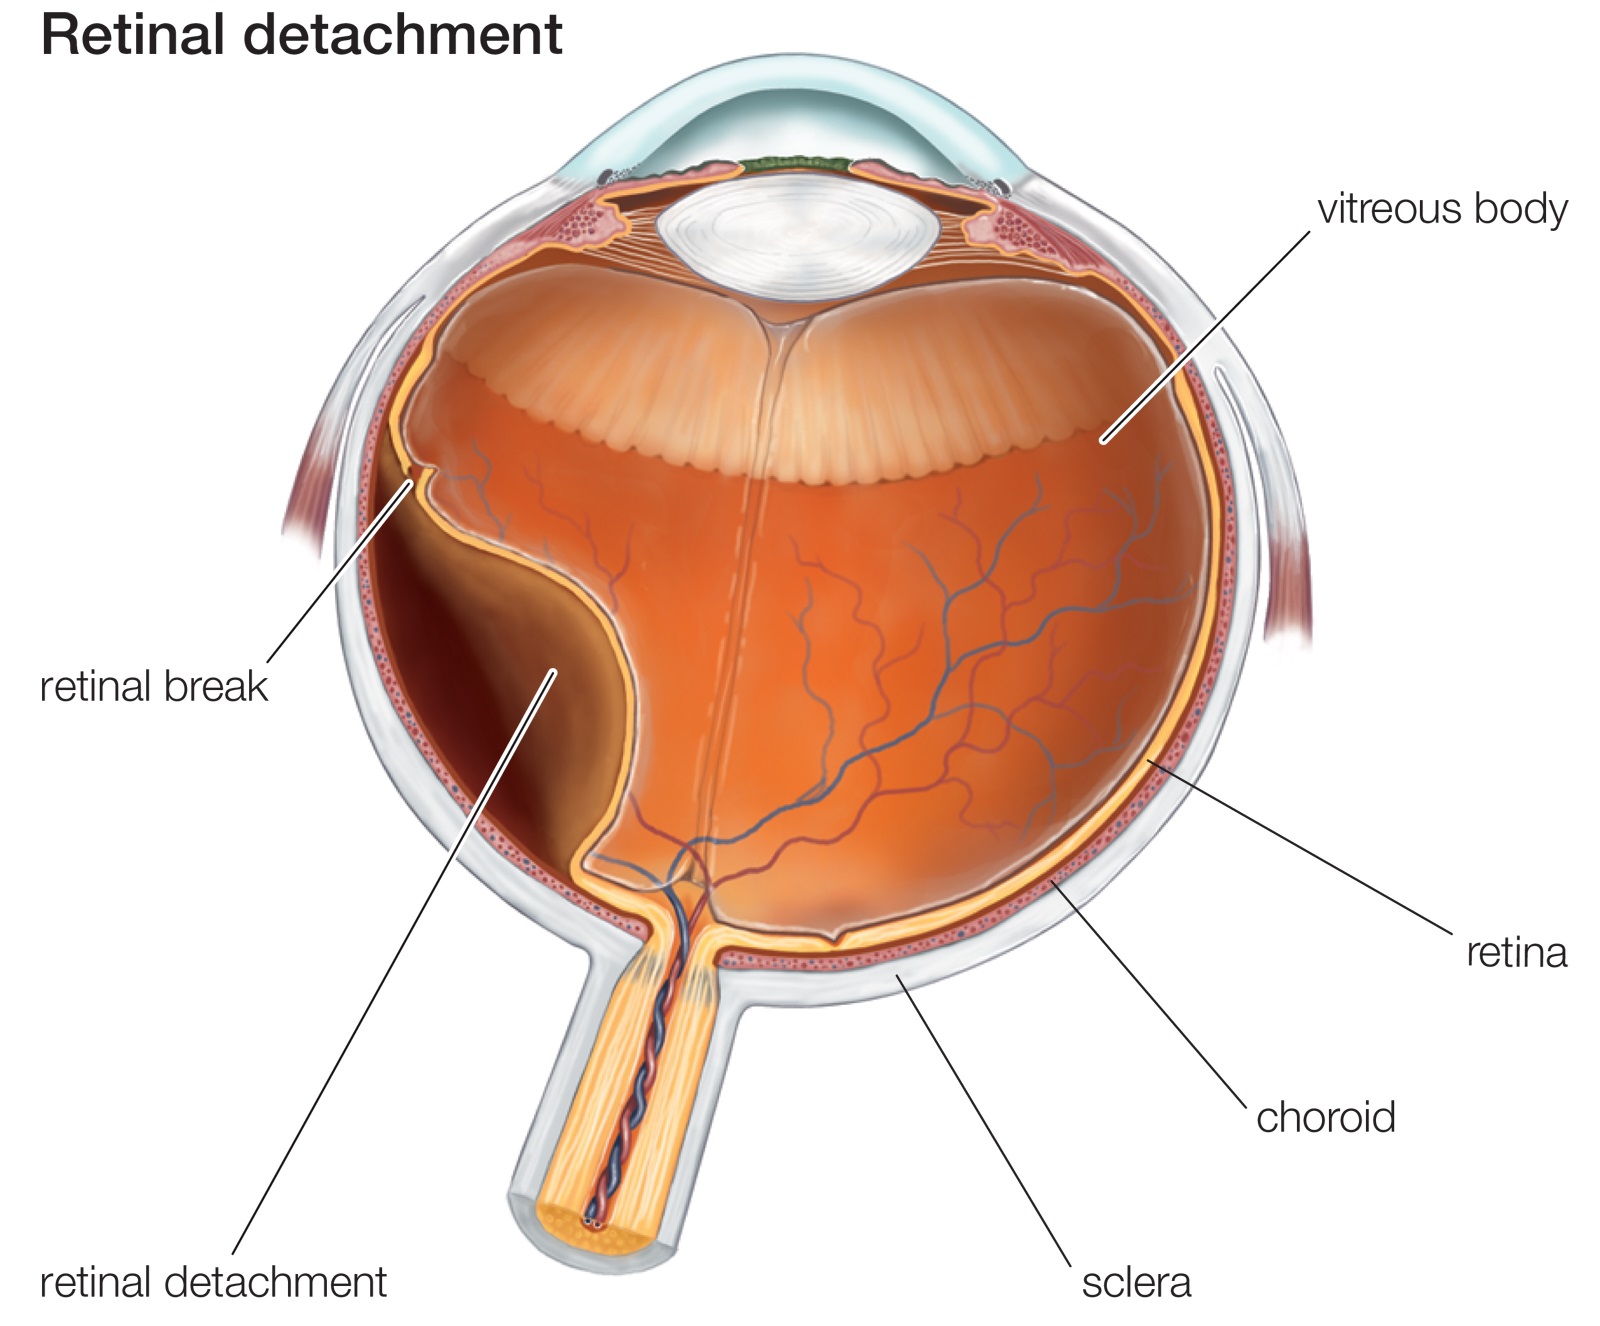

Detachment is the separation of rods and cones, we call them neuroepithelium, from the underlying pigment epithelium by the accumulation of fluid between them. This disrupts the power of the outer layers of the retina, which leads to rapid loss of vision.

分离是棒和视锥的分离,我们称它们为神经上皮,是通过它们之间的积聚而从下面的色素上皮中分离出来的。 这会破坏视网膜外层的力量,从而导致视力Swift丧失。

The reason for regmatogenous (regma — rupture) retinal detachment, or, they say, primary detachment, as is already clear, is a rupture or rupture of the retina. As a rule, the gap occurs somewhere on the periphery, close to the equator of the eye, in the area of thinning and dystrophy.

他们已经说过,视网膜变性或视网膜原发脱离的原因是视网膜形成或破裂。 通常,缝隙发生在变薄和营养不良的区域中,靠近眼睛的赤道的某个地方。

Comparing the eye with a camera in which there is a film, we can say that somewhere on the edge of the frame there appeared a scratch of the emulsion layer. Well, what of this, you say, because almost the entire frame and the most important thing — the center of the “composition” — is still visible well. It turns out that this is not true. Through the gap begins to penetrate the fluid, flowing under the retina and thereby peeling it from the underlying choroid. On film, it looks as if an emulsion layer starts to blister around the scratch and peel off from the substrate. A person at this moment sees a rather characteristic picture of a “gray curtain” at the edge of the visual field. Depending on the location of the gap, the “curtain” can either spread quickly (within several tens of hours), closing the entire field of view, or crawl more smoothly (for weeks)

将眼睛与装有胶卷的相机进行比较,可以说在镜框边缘的某个地方出现了乳剂层的划痕。 好吧,这就是您所说的,因为几乎整个框架和最重要的部分(“构图”的中心)仍然清晰可见。 事实证明这是不正确的。 穿过缝隙开始渗透流体,在视网膜下方流动,从而将其从下面的脉络膜剥离。 在胶片上,似乎乳液层开始在划痕周围起泡并从基材上剥离。 此时,一个人在视野的边缘看到了相当有特色的“灰色窗帘”图片。 取决于间隙的位置,“窗帘”可以快速传播(在几十小时内),关闭整个视场,或者可以更平滑地爬行(持续数周)

It is clear that if the gap is located in the upper parts of the eye, the fluid quickly goes down and the exfoliation passes rapidly. If the gap is located below, then the detachment slowly «crawls» up, and the progression will be slower. However, the adhesions between the retinal zones and scars will be more pronounced — the time for their formation will be more.

显然,如果间隙位于眼睛的上部,则液体会Swift下降,并且剥落会Swift通过。 如果间隙位于下方,则分离会缓慢地“爬行”,并且进展会变慢。 但是,视网膜区域和疤痕之间的粘连会更加明显-形成它们的时间会更长。

When retinal detachment the vitreous body never remains indifferent. In the initial period, only small violations of its structure are observed, manifested in the form of various inclusions floating in the field of view. With a long-existing detachment in the framework of the vitreous body, strands develop, which, like ropes, attach to the retinal surface and, slowly contracting, retract the retina to the center of the eyeball. This process is called vitreoretinal proliferation, which ultimately leads to the formation of the so-called «funnel» retinal detachment. In such a situation, reconstructive surgery is required, in terms of the quality of a much higher level. Close this gap seals is almost impossible, and not enough. The main task is to clean the surface of the retina from the strands of the vitreous body, straightening it.

当视网膜脱离时,玻璃体永远保持冷漠。 在最初阶段,仅观察到其结构的一些小违规,表现为视野中漂浮的各种夹杂物。 随着玻璃体框架内长期存在的脱离,会形成股线,就像绳索一样,股线会附着在视网膜表面,然后缓慢收缩,使视网膜缩回眼球中心。 该过程称为玻璃体视网膜增生,其最终导致形成所谓的“漏斗”视网膜脱离。 在这种情况下,就更高水平的质量而言,需要进行重建手术。 封闭这种间隙密封几乎是不可能的,而且还远远不够。 主要任务是清洁玻璃体股线的视网膜表面,使其变直。